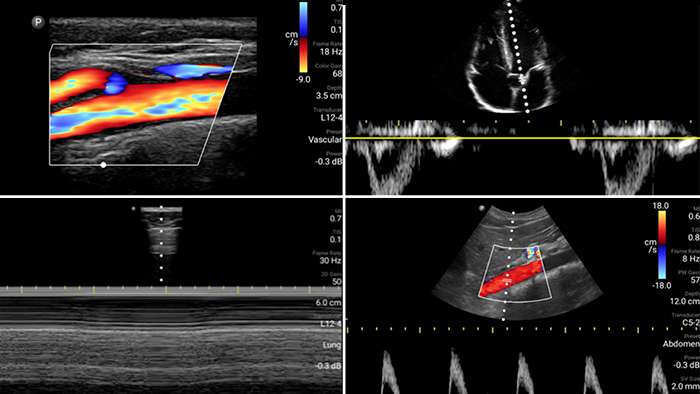

Lumify is with you

every step of the way

Evaluate, diagnose and treat your patients in

minutes with a multi-point POCUS exam.

Second case image

Lumify L12-4 broadband linear array transducer

• 12 to 4 MHz extended operating frequency range

• Aperture size: 34mm

• 2D, steerable color Doppler, M-mode, advancedXRES and multivariate harmonic imaging, SonoCT

• High resolution imaging for shallow applications: soft tissue, vascular, superficial, musculoskeletal and lung

Lumify S4-1 broadband phased array transducer

• 4 to 1 MHz extended operating frequency range

• 2D, color Doppler, M-mode, advanced XRES and multivariate harmonic imaging

• High-resolution imaging for abdominal and cardiac applications: Cardiac, OB/GYN, Lung, Abdomen and FAST imaging preset optimizations Lumify aids life-saving technology in prehospital setting